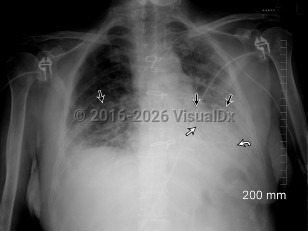

Acute interstitial pneumoniaAcute interstitial pneumonia

Drug-induced pneumonitis